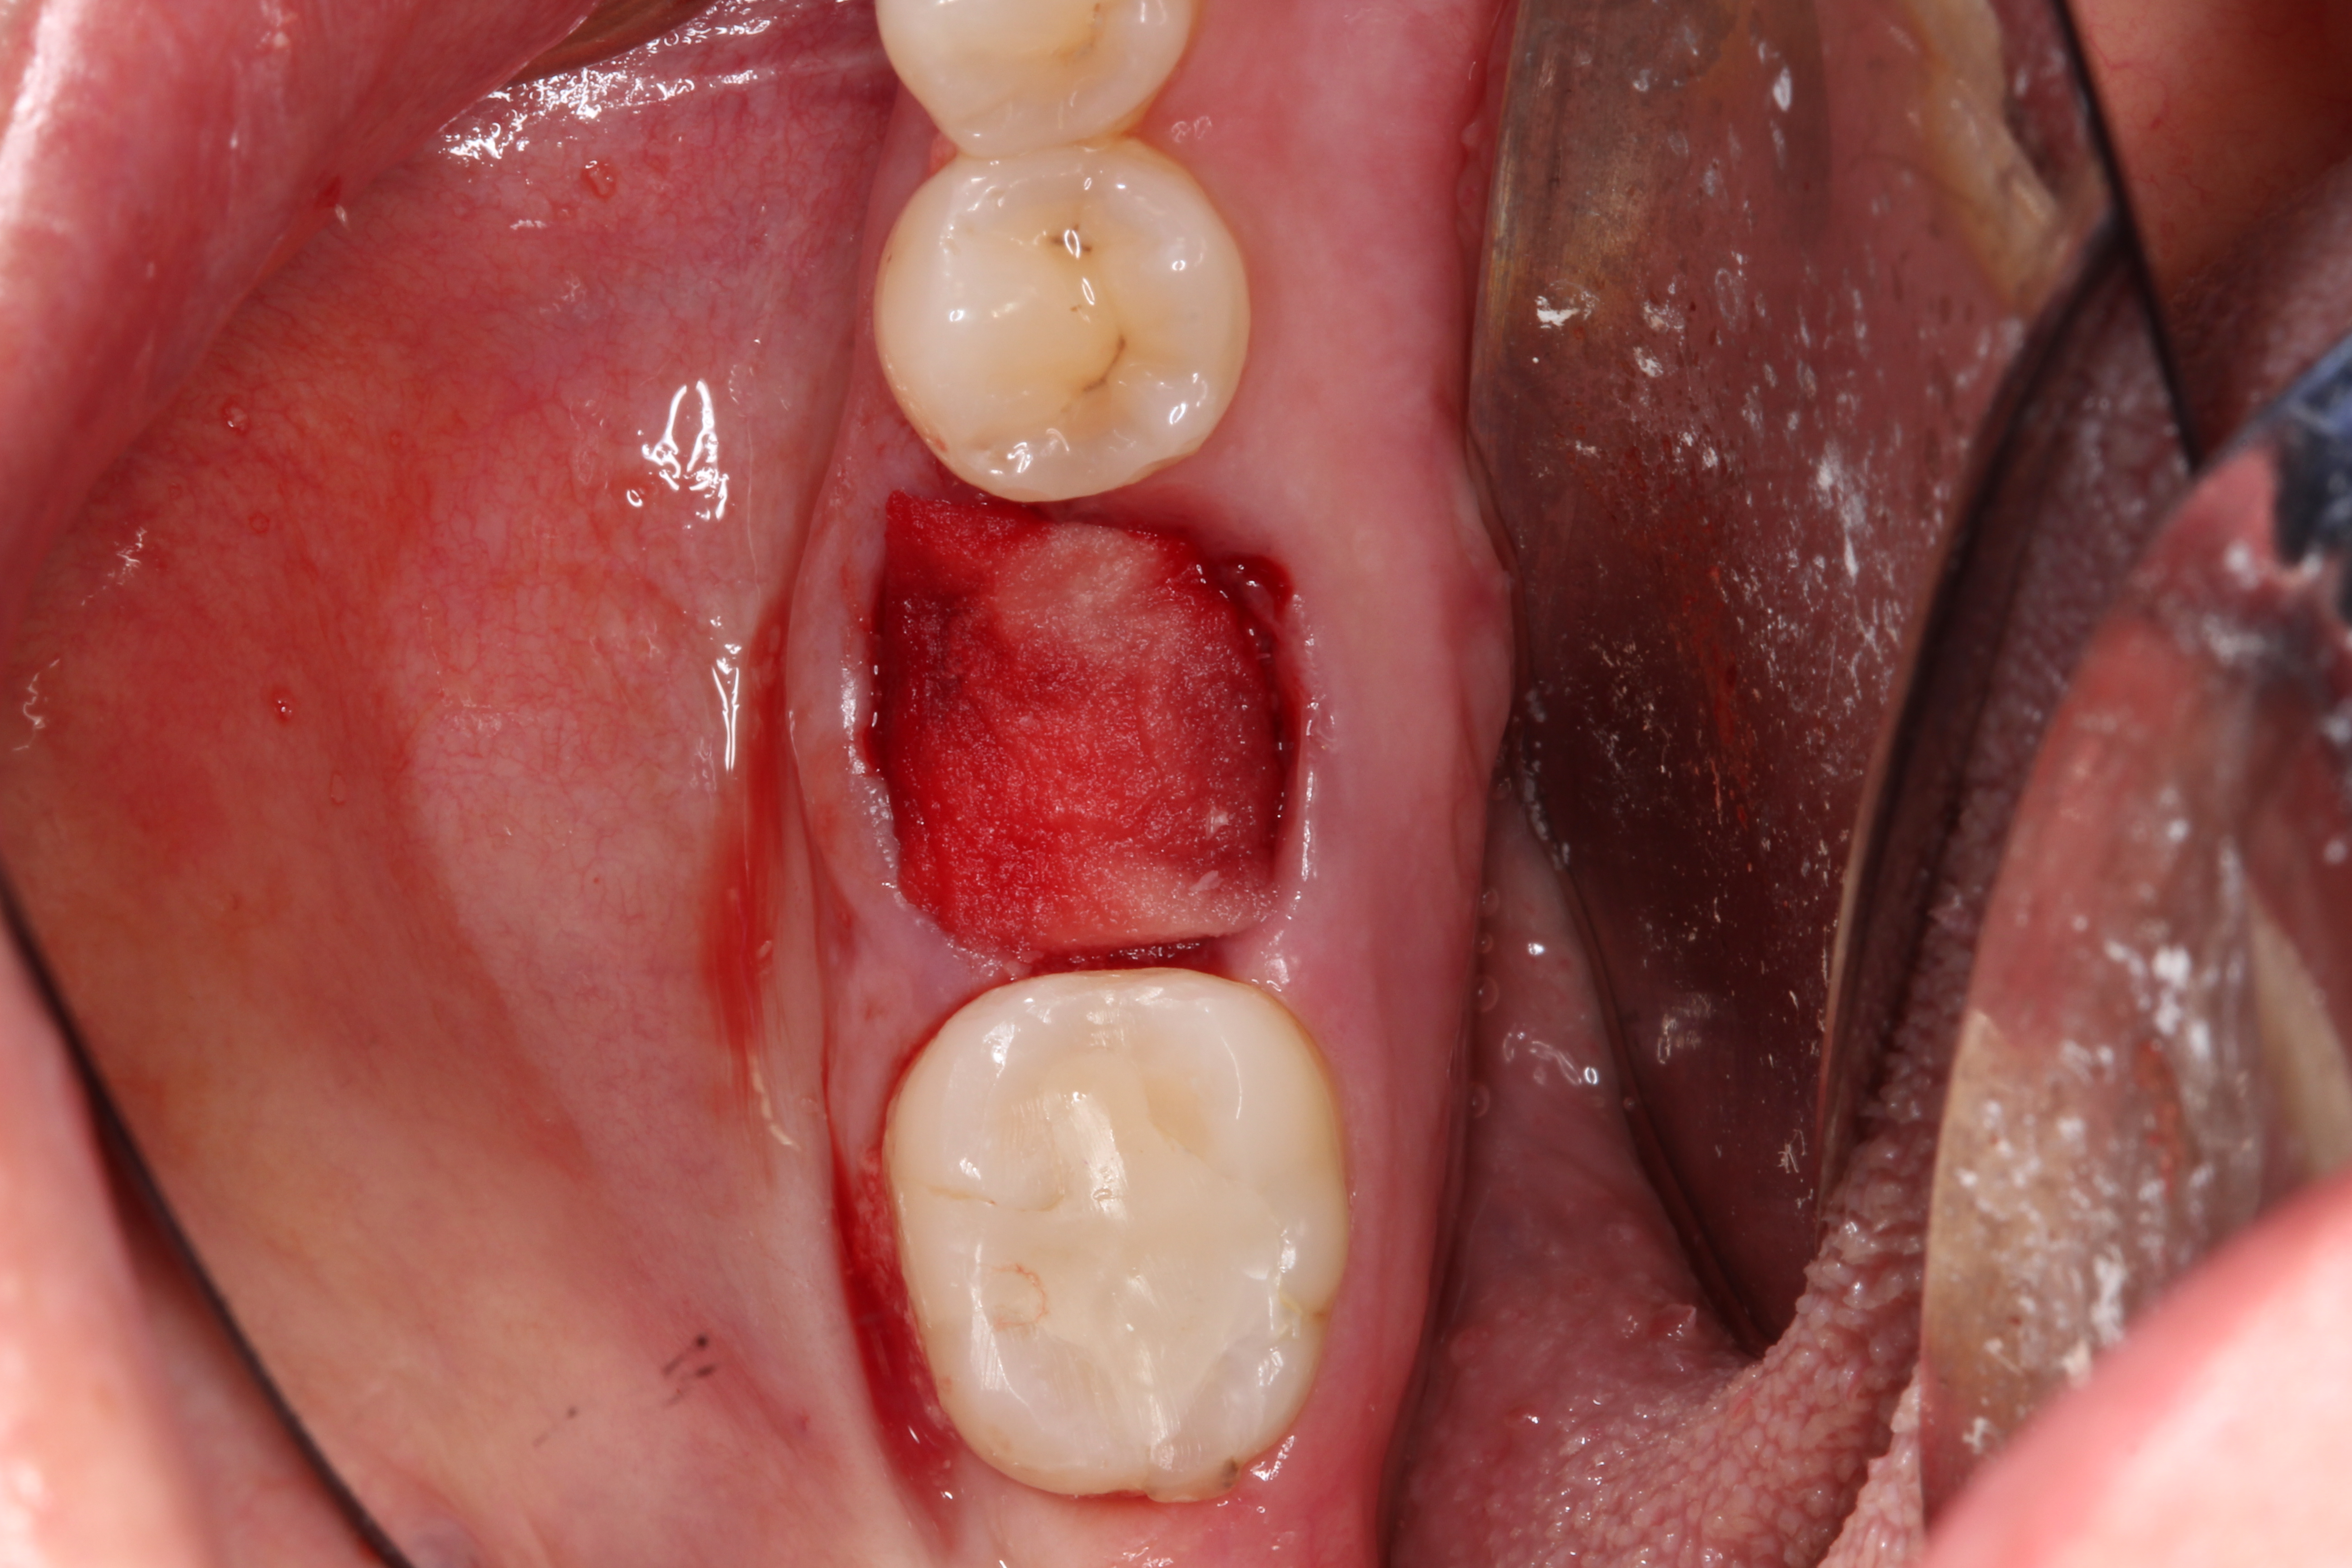

Fig 5. Clean any granulation tissue out of the socket to create a clean wound free of debris.

Figure 5

2. The remaining socket should be cleaned and curetted of all remaining granulation tissue or residual soft tissue present at the apex, especially with endodontically treated teeth (Figure 5).